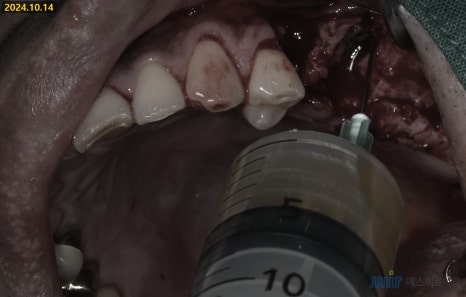

🔹1. 염증조직 제거, 발치

치아 발치 후,염증 조직을 제거했습니다

상악동 쪽 염증도 함께 제거하며

약 5ml 정도의 상악동 염증을 제거했습니다